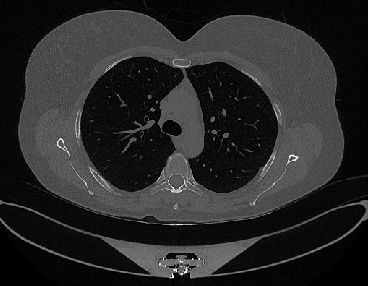

Figure 1 shows four CT scan slices, two from a non-COVID-19 CT scan, on the left and two from a COVID-19 scan, on the right. Bilateral ground glass regions are seen especially in lower lung lobes in the COVID-19 slices.